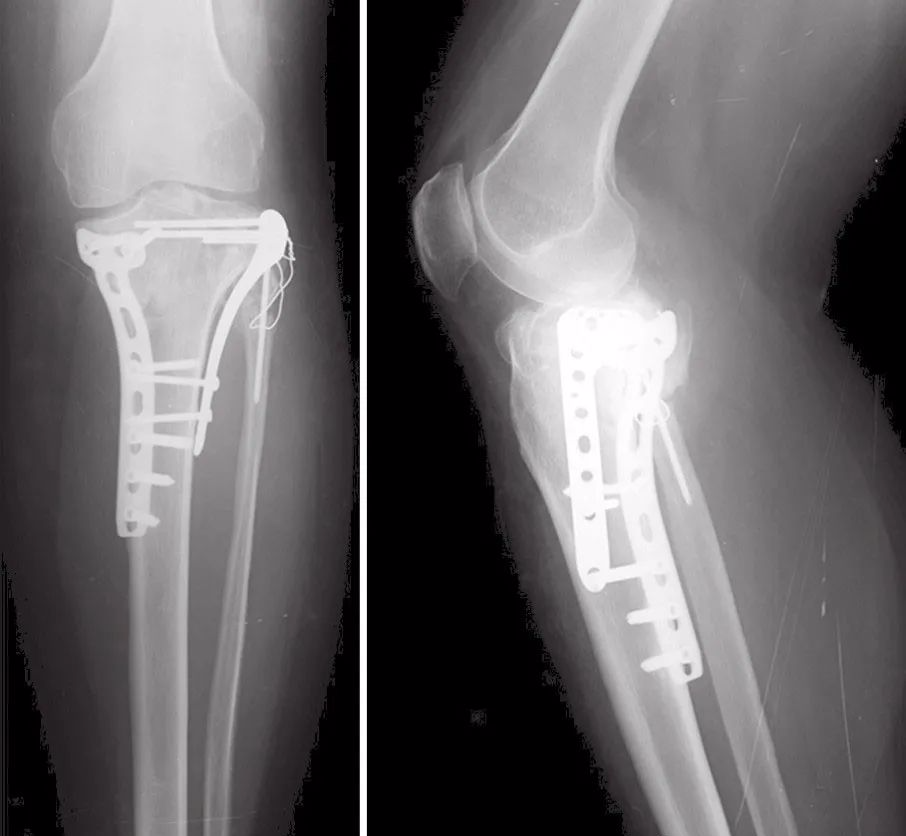

图22 术后1年随访的X线片

27岁男性患者,在交通意外中受伤。他从自行车上跌落,诉左膝严重疼痛,伤后无法站立。这是个单独的损伤。X线片(图17)和CT(图18~图20)显示左胫骨平台双髁骨折。用两块内固定钢板进行开放复位和内固定(图21)。患者术后1年,影像学表现良好(图22),临床功能(图23)恢复良好。